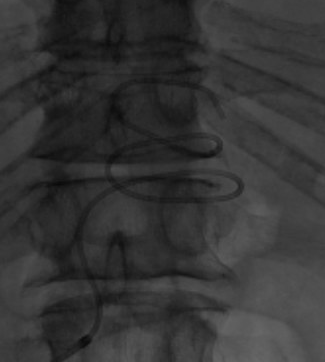

Option Elite filter in since February 2021 initially failed loop snare and forceps techniques, taken out with @PhilipsHealth #CavaClear laser sheath. 9 seconds of laser time. Great experience! #filterout @IrColorado @pj_rochon